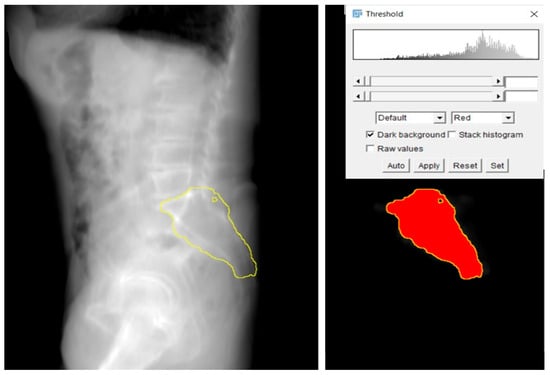

- 2D Projection Creation: From the 3D model, a 2D lateral view of the sacrum was generated by summing the Y-axis slices of the dataset. This 2D projection effectively reflected the bone density distribution within the sacrum and was crucial for visualizing regions of higher bone density. These areas were considered optimal for screw placement, as higher density regions are more likely to provide stable, intraosseous fixation.

- Generation of Screw Trajectory Target Zone: Using the 2D projection, a patient-specific safe zone for screw placement was identified through a reproducible computational technique developed in this study. The resulting zone is referred to as the Ramadanov–Zabler Safe Zone for reference purposes. Regions with higher bone density were targeted as they suggested a greater likelihood that the screw would remain strictly intraosseous, thereby reducing the risk of cortical breaches or screw misplacement. The target zone served as a guide for the ideal screw trajectory during percutaneous SI screw fixation.

3.3. Safe Zone Identification